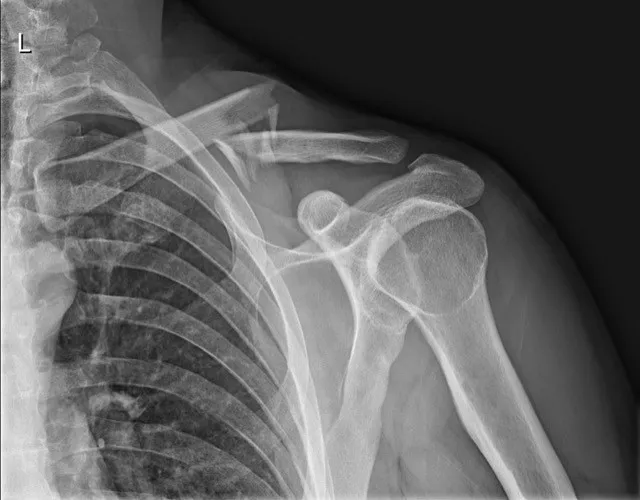

3. Beeldvorming: een röntgenfoto van de schouderregio bevestigt de sleutelbeenbreuk en toont de exacte locatie en de verplaatsing van de botstukken. Soms wordt bij complexe sleutelbeenbreuken of twijfel nog een CT-scan gemaakt om de breuklijn gedetailleerder in kaart te brengen.